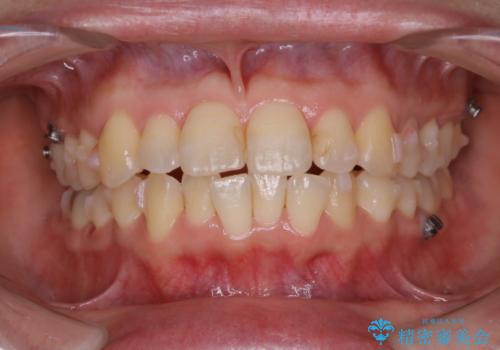

インビザラインで前歯の中心をお顔の中心に合わせる

- 右上の2番目の歯が内側に入っているのと、下の前歯のがたつきが気になるとご相談にいらした方です。

上下左右の歯を後ろに動かして歯を並べるスペースを確保し、内側に入っていた歯を綺麗に並べ、前歯の中心もお顔の中心に合うようにしました。

矯正用アンカースクリューを埋入し、上下左右の歯を後ろに動かすことで歯を並べるスペースを作りました。